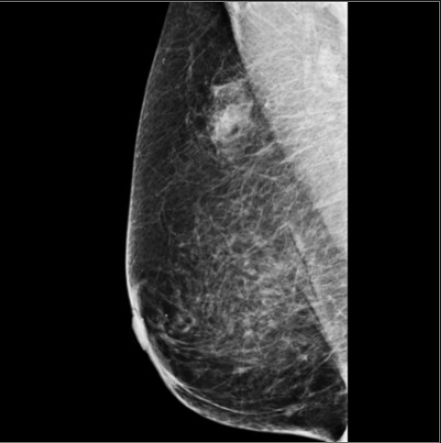

What is the echogenic halo secondary to?

Unresolved speculation and/or tumoral edema

Abrupt margins more likely to be benign

echogenic halo more likely to reflect malignancy (around70%)

(or wide transition zone)